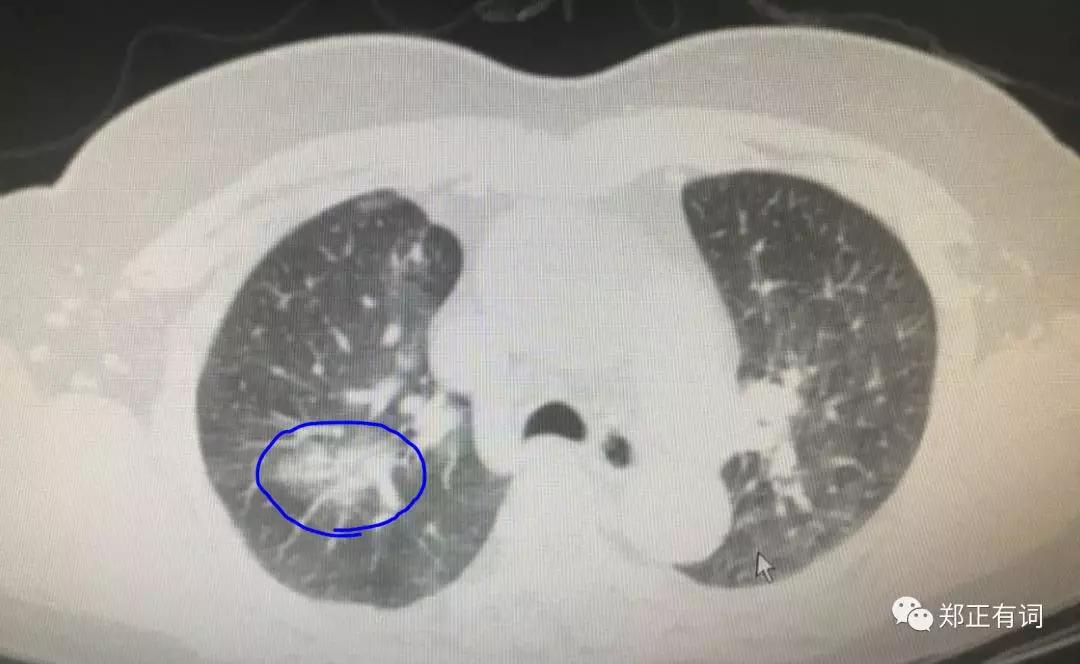

廖主任在患者的右上肺叶中找到了术前提到的两枚结节,经诊断均为恶性,因此,予以标准的右上肺叶切除及纵隔淋巴结清扫术,手术十分顺利。

术后的石蜡病理也进一步证实手术的必要性和有效性。

手术清扫淋巴结34枚,其中,纵隔清扫达29枚!

全部阴性,没有一枚转移~